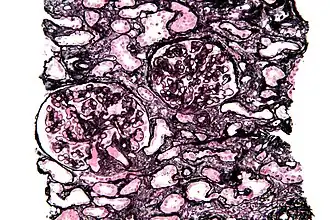

Tinción de Jones

La tinción de Jones, es una tinción de ácido peryódico de Schiff (PAS) y plata metenamina utilizada en patología.[1] También se conoce como metenamina PAS, que comúnmente se abrevia como MPAS .

Tiñe la membrana basal y se usa ampliamente en la investigación de enfermedades renales médicas.

La tinción de Jones muestra las proyecciones membranoides prominentes (spikes) de la membrana basal glomerular causadas por depósitos subepiteliales que se observan en la nefropatía membranosa .